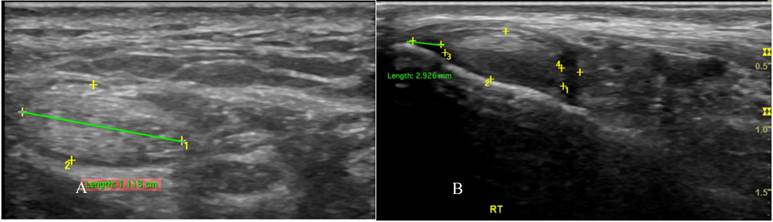

Figure 2

Transverse sonographic of posterior tibialis tendon with tenosynovitis showed thickening of the tendon fiber (A) with fluid in the tendon sheath (B).

Ultrasonography

PTT is well-assessed using US. We used a GE Logiq P9 ultrasound machine with an 18 MHz linear array transducer to scan the PTT. The position of the transducer in the PTT for ultrasound scanning is essential for obtaining accurate results. The subjects were placed in the lateral decubitus position. The PTT was scanned in longitudinal and transverse positions (Figure 1). Posterior tibialis dysfunction appears as tenosynovitis, tears, or tendinosis. The free fluid collection that created a hypoechoic lesion around the PTT and a sheath size greater than 7mm was tenosynovitis (hyperechoic central structure with a hypoechoic halo) on the ultrasound transverse position (Figure 2).[5, 22] A PTT tear or rupture appeared on ultrasound as an empty tibial groove with an intermuscular gap in the PTT (Figure 3). Tendinosis results in posterior tibial tendon thickening, with heterogeneous hypoechoic regions replacing the normal fibrillar architecture.[20]